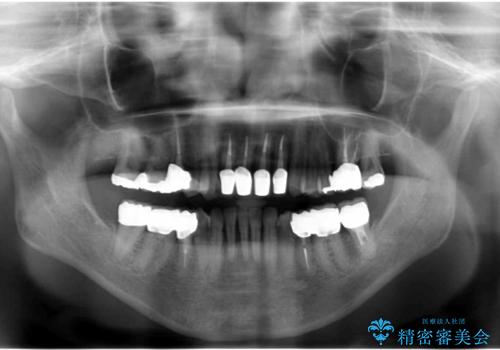

- 前歯の見た目・歯並び・銀歯の見た目の改善を求めて来院されました。

まずガタ付きの強い歯並びをマウスピース矯正インビザラインで整えたのち、セラミック治療による審美性の改善を計画します。

矯正治療が終わったのちに、精度の高いセラミックを装着することでより安定した噛み合わせとなり審美性も兼ね備えた口腔内状態で治療を終了し、今後のメンテナンスを行っていくことができます。